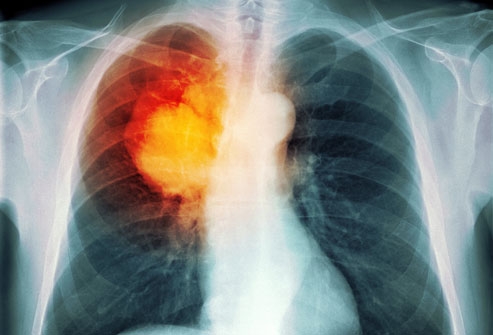

Trong hầu hết các trường hợp, khi bác sĩ nghi ngờ bệnh nhân mắc ung thư phổi với các triệu chứng điển hình như ho mãn tính hoặc thở khò khè, lúc đó, bác sĩ sẽ cho người bệnh đi chụp X-quang hoặc các xét nghiệm hình ảnh khác. Bệnh nhân cũng có thể được yêu cầu xét nghiệm đờm. Nếu một trong các xét nghiệm cho thấy xuất hiện dấu hiệu của ung thư, bước tiếp theo bác sĩ sẽ tiến hành sinh thiết phổi.